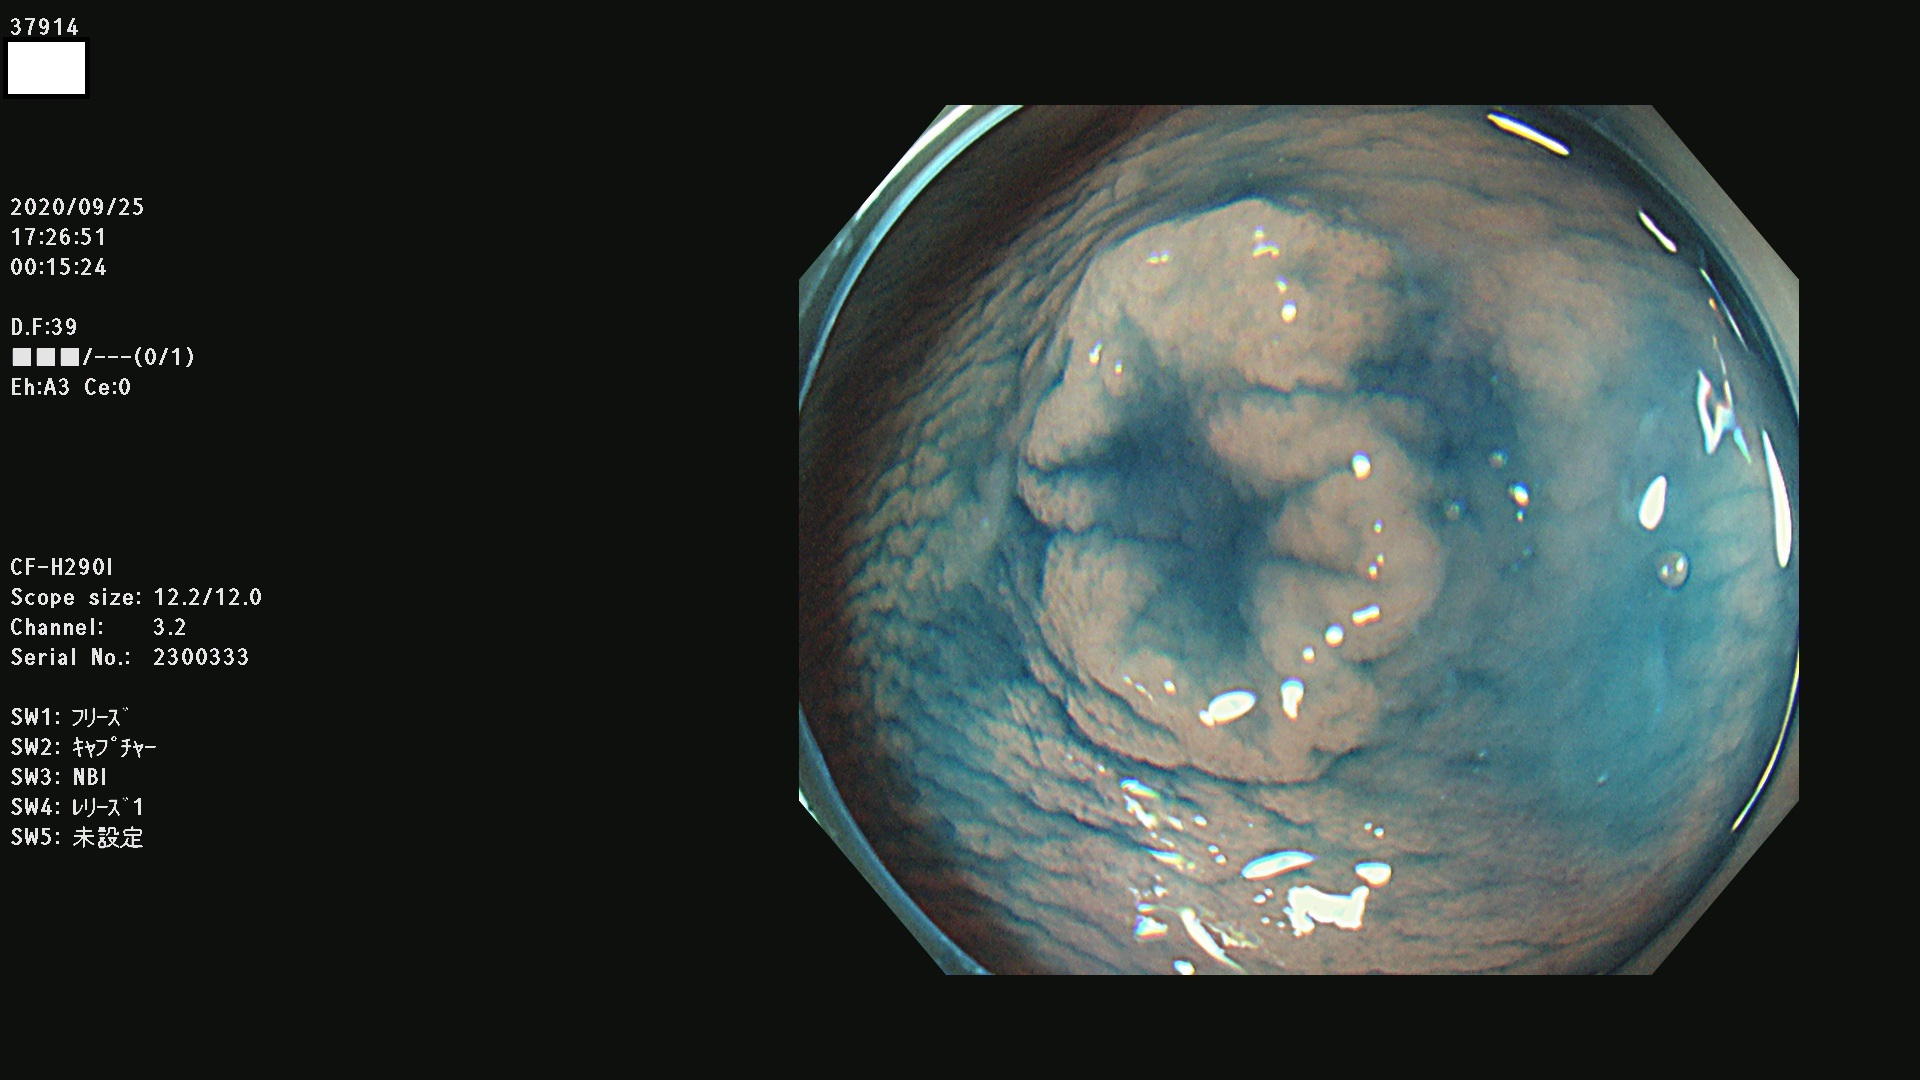

37900 37902 37903 37904 37905 37906 37907 37909 37910 37911 37912 37913 37914 37915 37916 37917 37919 37921 37922 37923 37926 37928 37929 37930 37931 37933 37934 37935 37936 37937 37938(SSAPのみ) 37939 37940 37941 37942 37943 37946 37947 37948 37949 37951 37952 37953(SSAPのみ) 37955 37956 37957(SSAPのみ) 37958(SSAPのみ) 37960 37962 37963 37964 37966 37967 37968 37971 37972 37973 37975 37976 37977 37979 37982 37983 37984 37985 37986 37987 37988 37989 37990 37991 37992 37993 37994 37995 37996 37998 37999

発見困難で危険性の高い平坦型病変(上記100名より抽出)